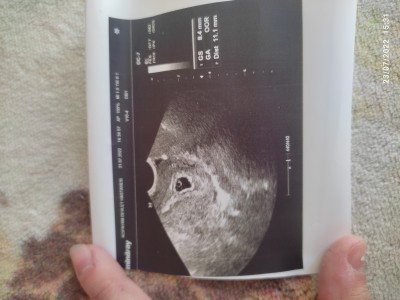

Kizlar doktora gittim burda kese varmi? Icindeki bebekmi?

Gebelik haftası 5+3

Gebelik kesesi ve yolk sac car canım bebekte olusur 1 2 haftaya :)

Bebek yok sanirim içinse canım yada olcmemjs de olabilir crl yazsaydi kenarda bebek boyunu söylemiş olurdu kese boyutunu olcmus

Benimkide öyleydi gebeliğin var canım 1  2 haftayada kalp atışlarını duyarsın benim ultrason da tıpkı seninki gibiydi ordaki nohut gibi yuvarlak olan bebeğin deöişti doktorum

O bebegin plasenta olacağı yolk kesesi haftaya bebegide görürsün canım hayırlı olsun

Kesede yolk sac varsa bil ki bebek de vardır o boş gebelik olmaz o zaman doktor bana öyle söyledi çünkü daha önceden biliyorum bunu İnşallah haftaya kalp atışını duyarsın öyle görünüyor zaten